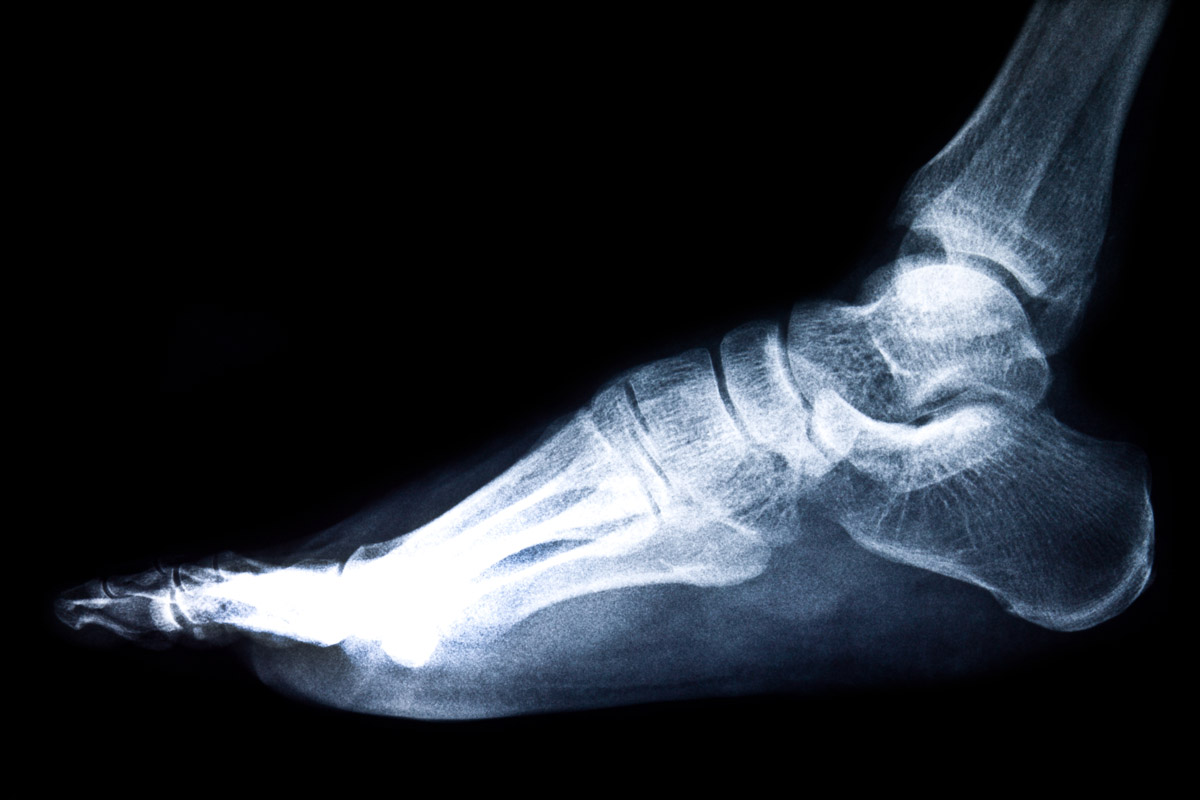

Избавиться от патологии стопы поможет только квалифицированный врач после осмотра и сбора всех необходимых данных. Диагностика боли в ступне с внешней стороны включает следующие методы:

Основные методы диагностики боли в ступне с внешней стороны

Методика диагностики Время

Рентгенография стопы 15-30 минут

УЗИ стоп 30 минут

КТ стопы 15 минут

МРТ стопы 20 минут

Каждый из этих методов даст информацию о состоянии костей, мышц, сухожилий, сосудов и кожных покровов стопы. Пройти обследование можно в любом медицинском учреждении, которое оснащено необходимой аппаратурой. Стоимость диагностических методов разнится. Самым бюджетным считается ультразвуковое исследование. Его цена начинается от 1110 рублей. Самыми дорогими принято считать компьютерную и магнитно-резонансную томографии. Стоимость этих процедур начинается от 4000 рублей. Но точность получаемых данных полностью оправдывает затраты.